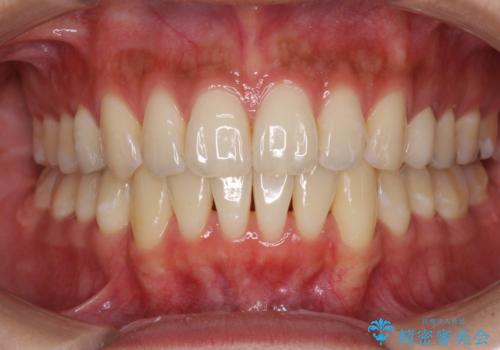

八重歯の再矯正 インビザラインでストレスなく矯正治療

下顎の八重歯が上顎歯列に収まる過程で咬みにくさがありましたが、最終的には、咬み合わせも安定し、きれいに歯列を整えることができました。

矯正治療後には根管治療を行った歯の補綴治療を行うこととしました。